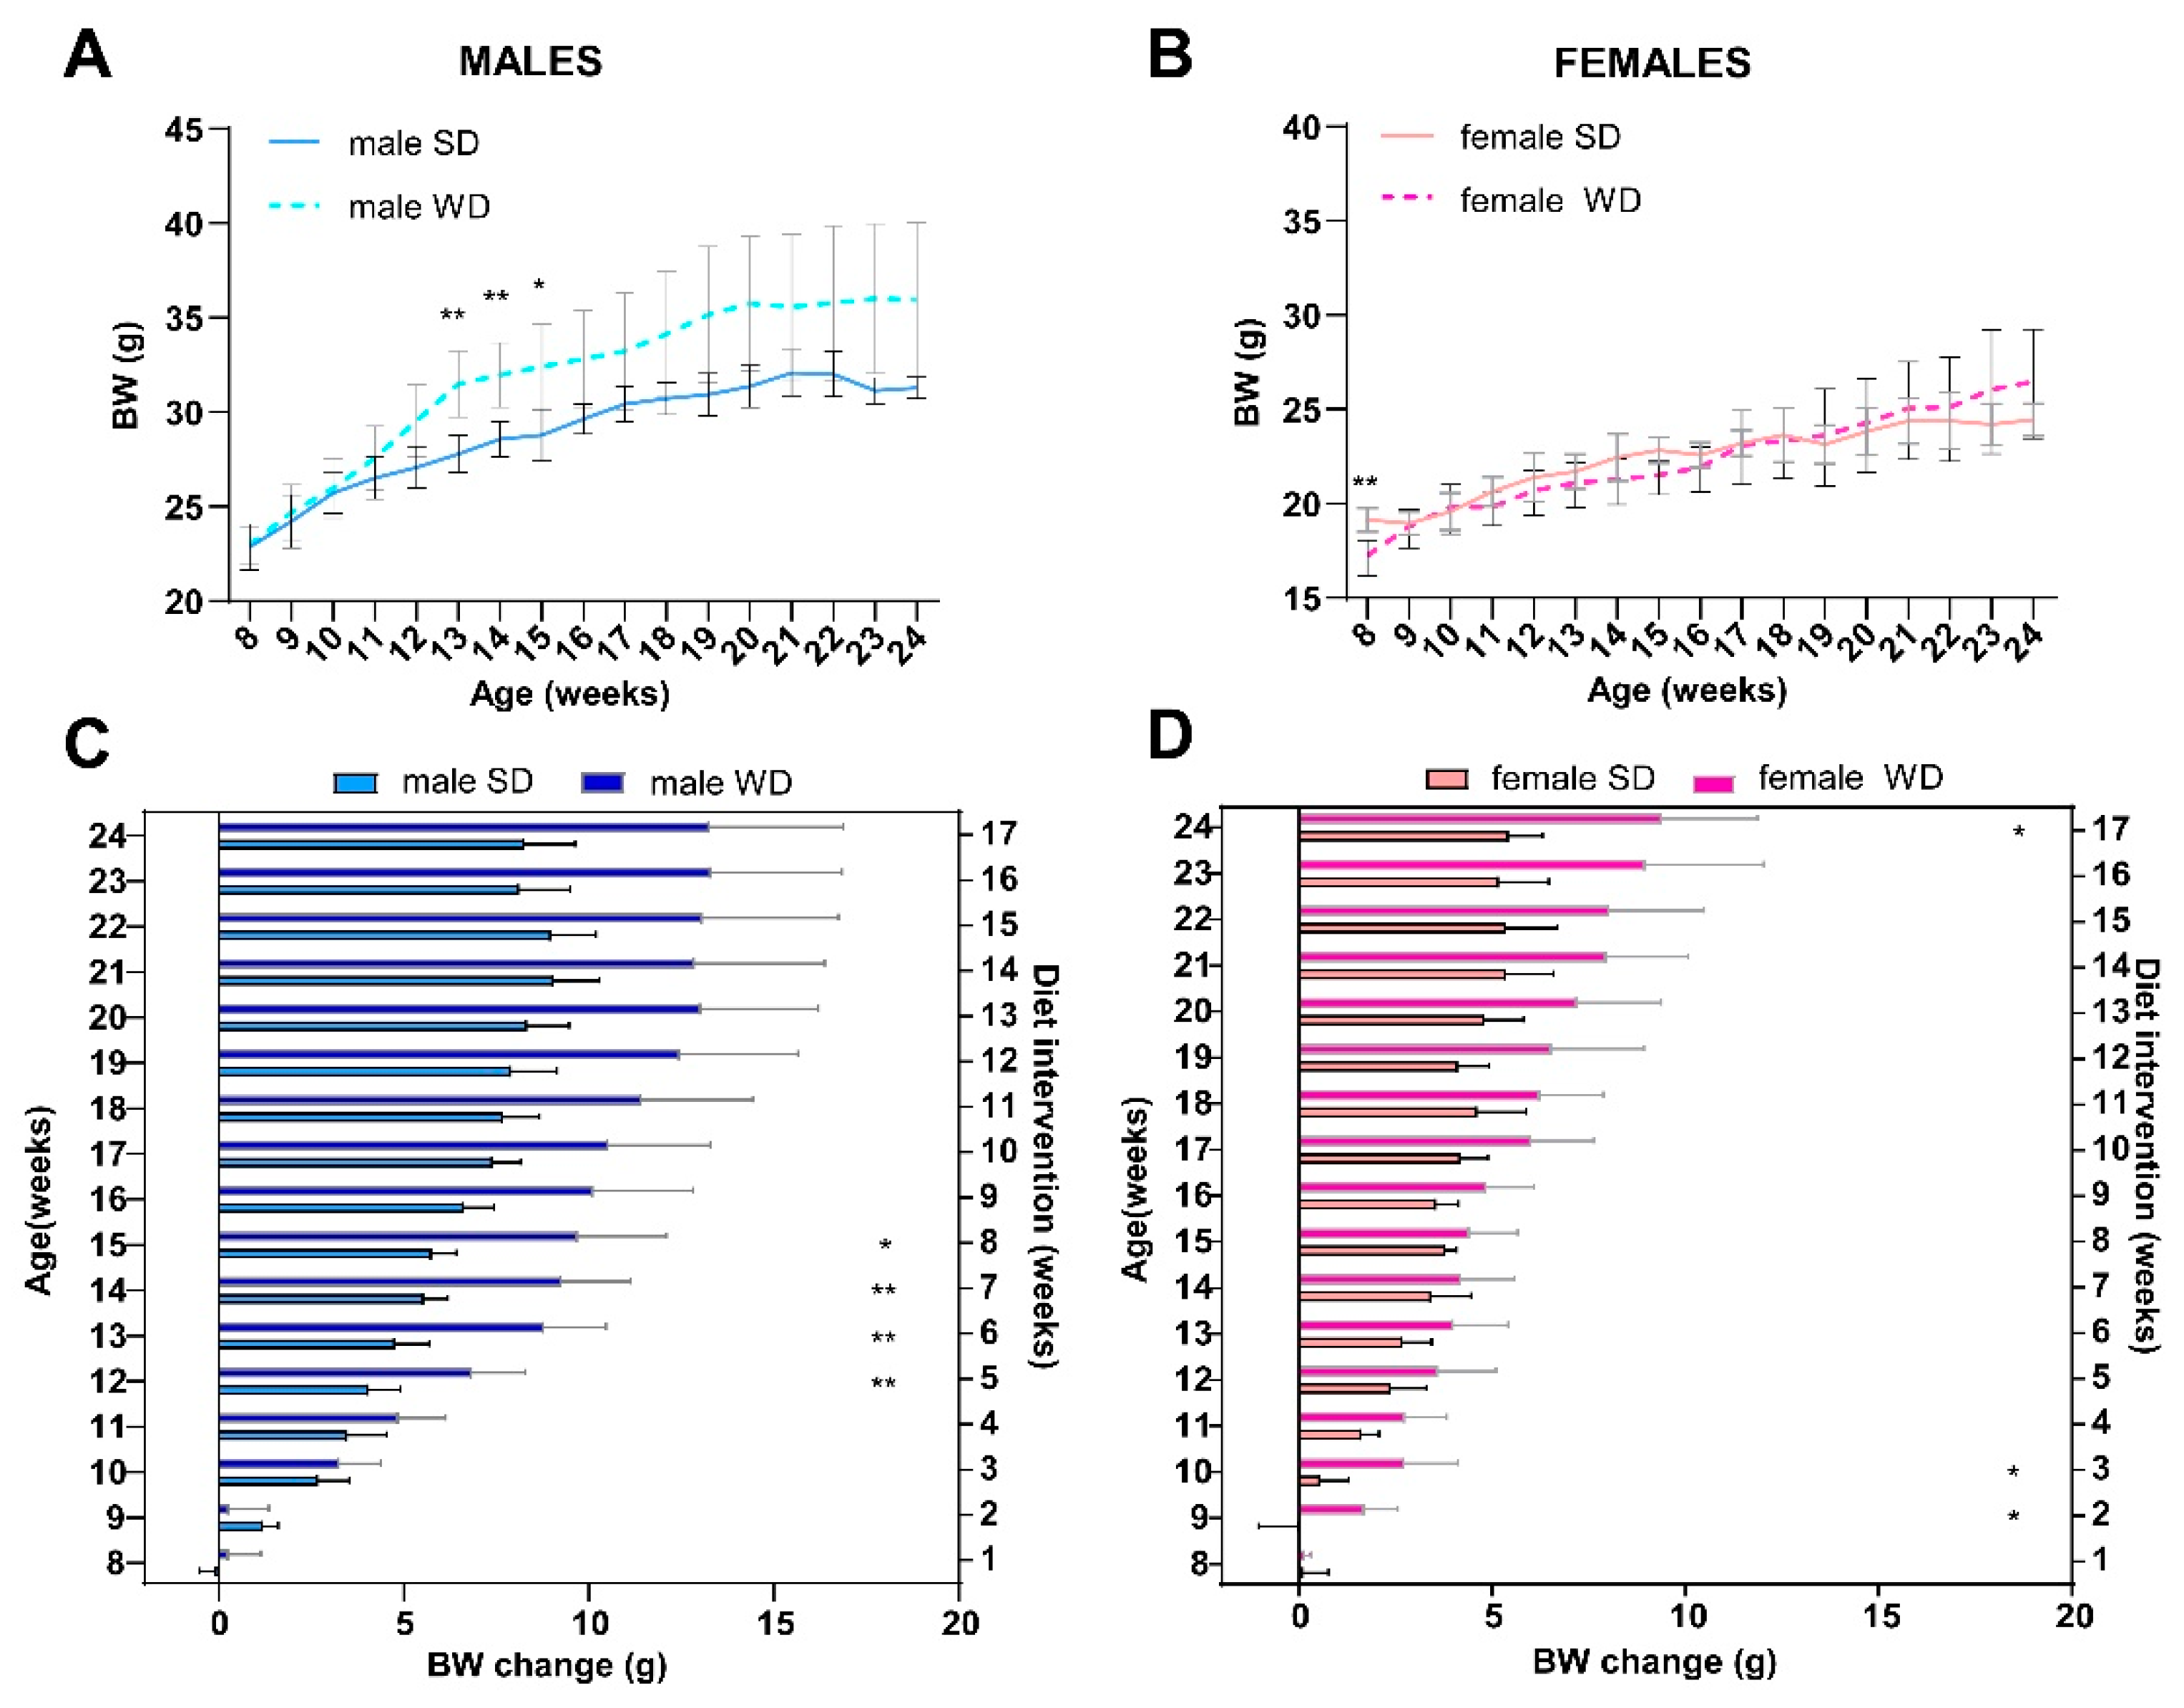

3.1. WD Affects Body Weight and Nutritional Phenotype of C57Bl/6J Mice